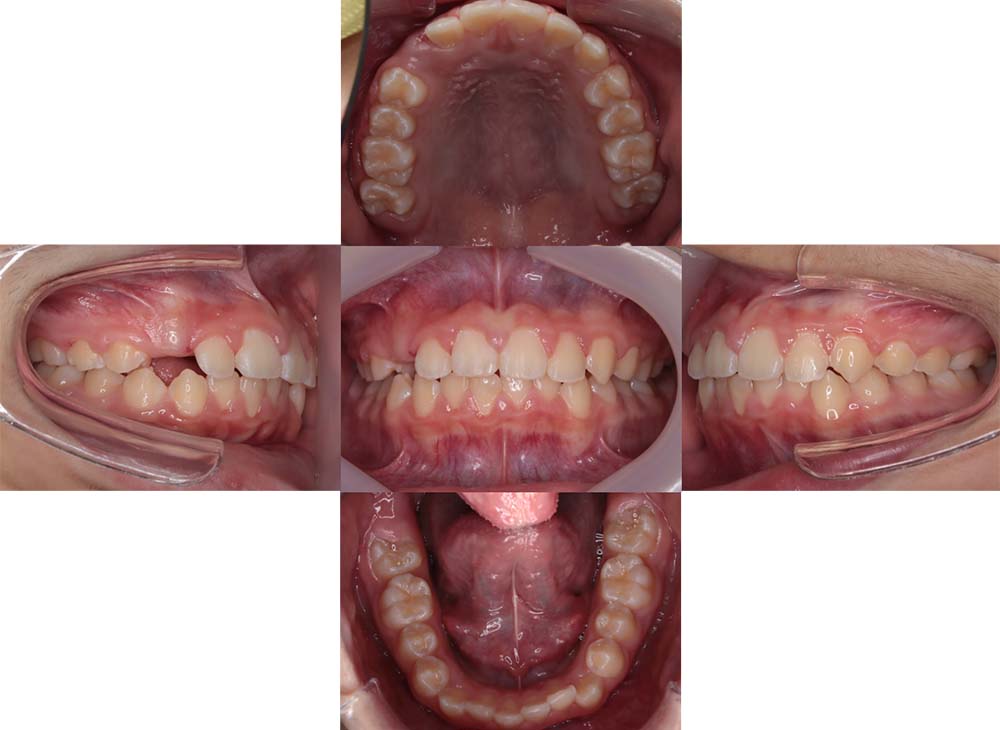

症例02

| 主訴 | 下あご顎が出ている。曲がっている。 |

| 診断名あるいは主な症状 | 反対咬合、非対称、空隙歯列、過蓋咬合 |

| 年齢/性別 | 19歳・女性 |

| 矯正ステージ | 大人の矯正治療 |

| 治療方法 | ワイヤー矯正、顎矯正手術の施行 |

| 抜歯部位/抜歯有無 | 非抜歯 |

| 治療内容 | 上下顎歯列を並べた後に顎矯正手術の施行。 |

| 費用 | 保険治療 |

| 治療期間 | 3年2ヶ月 |

| 主なリスク・副作用 | 痛み、歯根吸収、歯肉退縮、虫歯、後戻り |